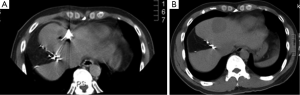

Case discussion 2 (Figure 6)

A 45-year-old woman with a diagnosis of diffuse liver metastases due to colon cancer requires a chemotherapy holiday due to neuropathy from therapy. She has been treated with FOLFOX and FOLFIRI. Given the diffuse nature of her liver metastases and clinical situation, Y90 radio-embolizaiton was recommended. Chemoembolization was considered to be an option but available results have shown better outcomes for smaller volume disease.

Case discussion 3 (Figure 7)

A 54-year-old man with a remote history of rectal cancer is found to have a new solitary liver metastasis measuring 2 cm. The patient has agreed to receive chemotherapy. RFA was recommended by the multidisciplinary liver tumor board given its long track record and good success in tumors <3 cm.